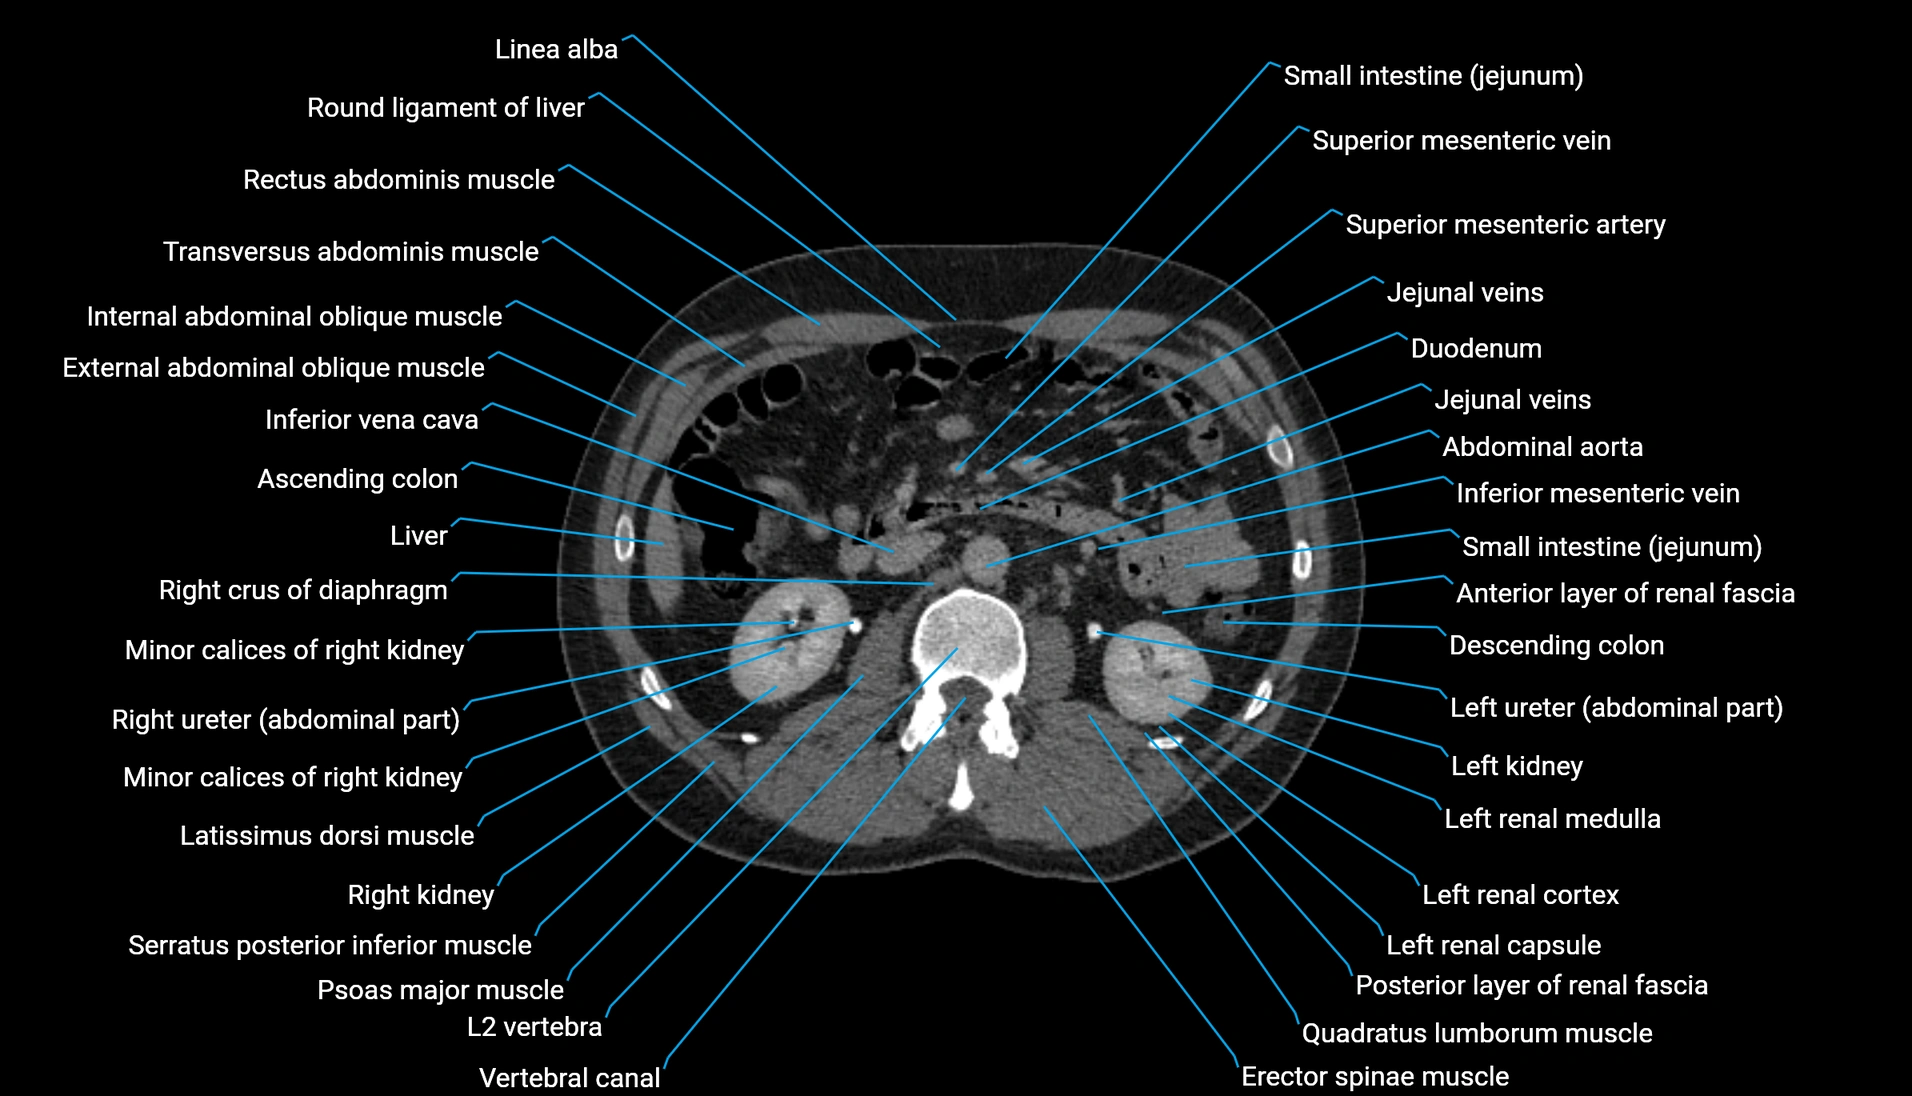

CT image